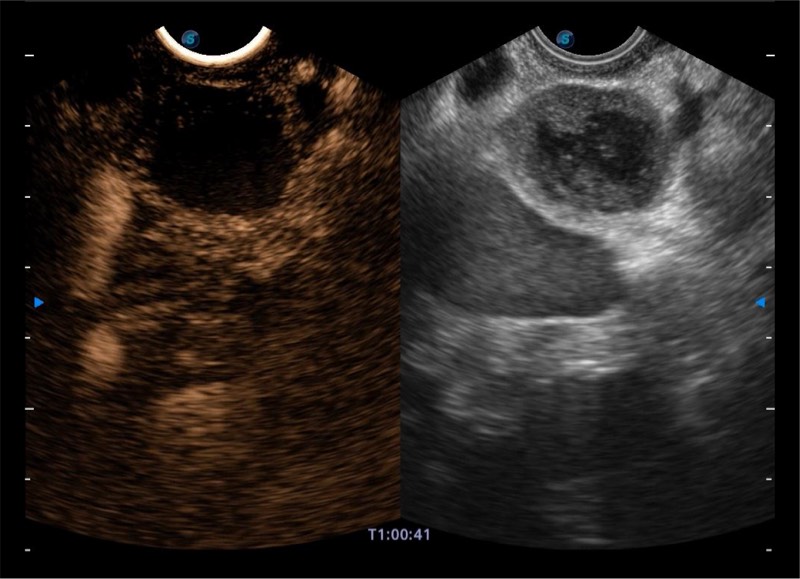

搭载百万级CMOS成像技术

及自主研发凸阵换能器,

可呈现优质的内镜和超声画面

基于二十年的超声技术积累,竞技宝(JJB)官方网站提供了最新一代的独立超声主机,在提供高质量图像的同时满足多学科使用。具备常见多普勒技术并提供弹性成像、声学造影等高端影像技术。新一代传感器具有更强的抗干扰能力并减少图像伪影。

4-12MHZ宽频输出